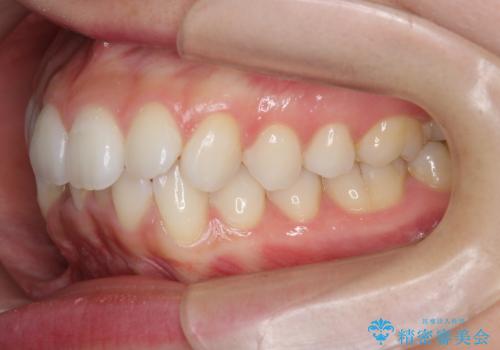

- 前歯が出っ歯のように見えることの改善を求めて来院されました。

当初、セラミックによる治療をご希望されていましたが、相談の結果矯正治療を選択されることとなりました。

通常口元の突出感の改善を行うには小臼歯の4本抜歯が検討されますが、歯のガタ付きが下顎前歯に限定していることから

下顎前歯を1本だけ抜去を行い、上顎の歯は可及的にマイクロインプラントを用いた後方移動を行い口元の印象の改善を計画することとなりました。

マイクロインプラントを用いてしっかりと後方移動を行ったことで前歯の角度は改善され、口元もすっきりと仕上げることができました。